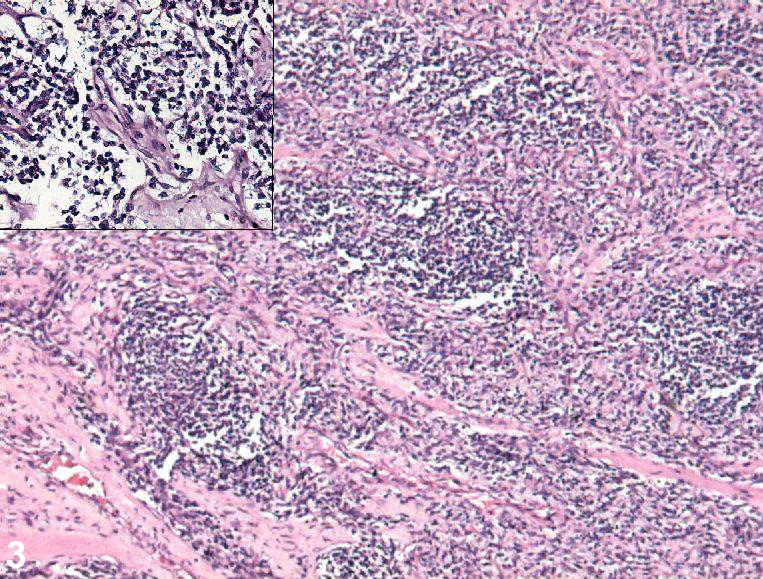

Definitive diagnosis of liposarcoma is made by pathology showing malignant proliferation of adipose tissue.

Lipoblasts are the characteristic cells seen in liposarcoma.